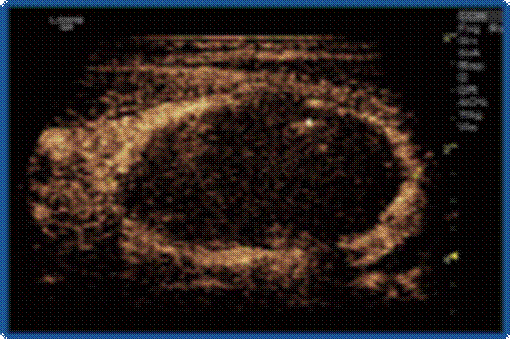

甲状旁腺腺瘤(↑)导致甲旁亢;术前超声造影示血供丰富(↑) ;

术后超声造影提示病灶呈无增强,完全坏死(↑) ;